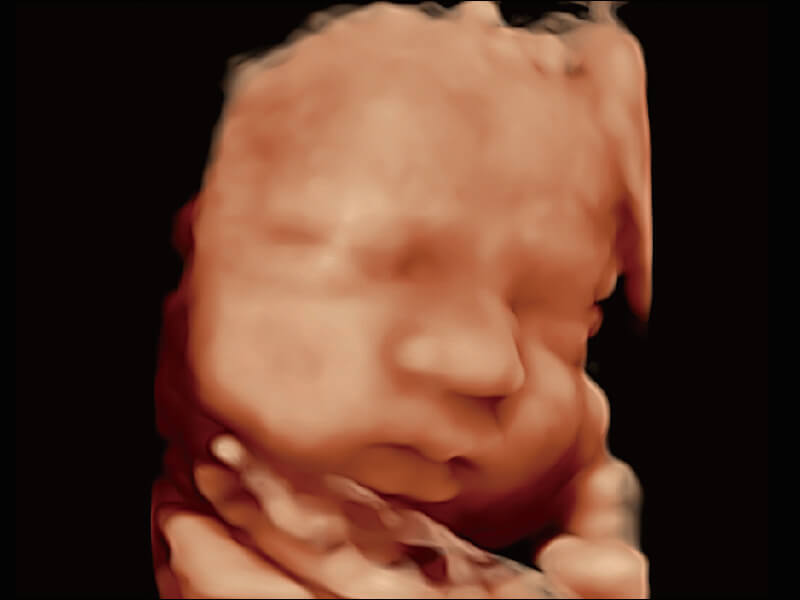

超宽频带技术,为容积成像带来优质的二维图像基础,为您呈现丰富的结构细节,栩栩如生地展示宝宝的宫内形态以及各种组织的立体结构。